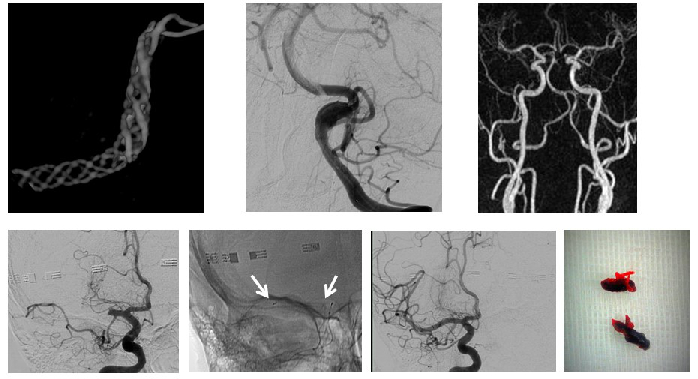

Dual-Energy CT in Stroke Patients

Assoz.-Prof. Grams, Dr. Janjic, Dr. Mangesius, Dr. Pereverzyev in cooperation with Prof. Kiechl, Prof. Knoflach and Prof. Haltmeier (LFU)

The detection of acute cerebral infarction is crucial in order to decide on further treatment. By comparison with conventional CT, early infarctions can be identified better with dual-energy CT (Fig. 2). A recent research project aims to predict infarction development prior to its visualisation, by using radiomics features in dual-energy CT datasets.